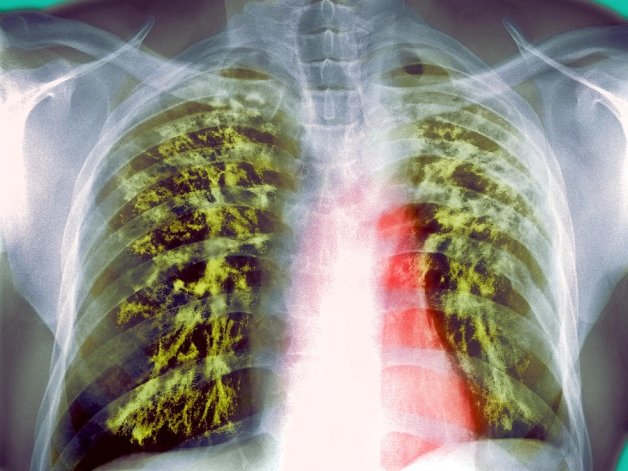

نتایج یک تحقیق نشان میدهد موسیر میتواند به مقابله با مقاومت آنتیبیوتیکی در بیماری سل کمک کند.

به گزارش ایسنا، گروهی از متخصصان انگلیسی در یک بررسی دریافتند موسیر میتواند به مقابله با مقاومت آنتیبیوتیکی در بیماری سل کمک کند.

متخصصان معتقدند خواص آنتی باکتریال گرفته شده از موسیر تاثیر درمانهای آنتی بیوتیکی جدید را افزایش میدهد و میتواند به معکوس کردن روند افزایشی مقاومت دارویی سل که در سال ۲۰۱۶ حدود ۴۹۰ هزار نفر را آلوده کرده، کمک کند.